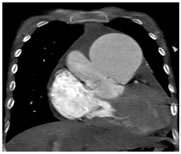

Figure 3:

Changes of pulmonary hypertension: In our study, 12 (48%) patients showed changes of pulmonary hypertension in the form of dilated main pulmonary artery with or without their branches dilatation. 7(28%) patients showed right ventricular and right atrial hypertrophy. Chamber status: In our study 7(28%) patients showed right ventricular and right atrial hypertrophy.2 cases showed double outlet single ventricle, 1 case with double chambered right ventricle with right atrial and right ventricular dilatation ,2 cases showed dilated RA with atrialization of RV. One case showed left sided juxta position of atrial appendages with double outlet left ventricle and hypoplastic right ventricle. The septal defects with resultant interchamber communication are already taken into account. Anomalous pulmonary venous communication: In our study there 8 patients with anomalous pulmonary venous communication (APVC). Out of this 4 were total anomalous pulmonary venous communication (TAPVC). Of these 4 patients of TAPVC, two were with supra cardiac TAPVC , one was with cardiac and one with infra cardiac type. Persistence of left superior vena cava SVC: In our study 5 (20%) cases showed persistence of left SVC. Patent ductus arteriosus (PDA): In our study 5 (20%) cases showed patent dustus arteriosus.